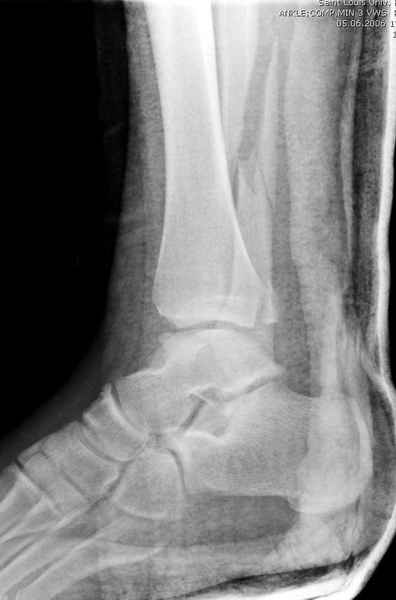

Неравномерность суставной щели может быть связана с разрывом глубокой порции дельтовидной связки и ротацией м/берцовой кости за счет поврежденных структур синдесмоза(репозиция ее на уровне перелома как-будто удовлетворительная).

По моему мнению,ассиметрия суставной щели обусловлена импрессией медиальной части суставной поверхности б/б кости. Да, позиционный винт здесь не лишен, но через 4 недели целесообразность его проведения сомнительна, брейс, ограничение осевой нагрузки достаточно.Есть еще деонтологические аспекты повторной операции, не все так плохо выполнено предыдущим доктором!

Импрессия медиальной части суставной поверхности бывает при супинационном механизме перелома лодыжек (тип А по классификации АО). Здесь механизм пронациия+наружная ротация (тип С, синдесмоз и межкостная мебрана повреждены),

перелом медиальной лодыжки отрывной, при этом в 20-30% бывает повреждение дельтовидной связки.

Клиновидность щели сустава следствие повреждения дельты, невосстановления длины малоберцовой или (хотел сказать "установки в гипсе", но оного, вроде,

нет)? Устранить бы причину. А равно как и тенденцию" к наружному подвывиху. Чрескостный остеосинтез - метод выбора.

Мое мнение, что никакой ротации малоберцовой кости здесь нет и синдесмоз тоже впорядке. Все дело в некачественно репозиции медиального мыщелка. Скорее всего его или немного ротировали при операции или сместили латерально. Более склонен ко второму варианту.

Конечно, компьютерный томограф более информативный метод, но с помощью недорогого обычного стандартного в нейтральном положении стопы: прямого, бокового и косой (ankle mortise) ренгенологического метода можно получить полную информацию о повреждении голеностопного сустава, а сравнительный снимок с другой стороны подтвердить наличие повреждения.

При реконструкции голеностопа, о важности восстановления длины малоберцовой для профилактики пост травматического артроза разбирали в предыдущих дискуссиях. Нарушенную биомеханику голеностопа без восстановления длины малоберцовой, не восстановить только швом медиальной связки.

Расширенная медиальная щель более чем на 4 мм и укорочение малоберцовой более чем 2 мм, а перелом заднего края большеберцовой смещения более 2мм с вовлечением 30% поверхности сустава, считается отходом от нормы голеностопного сустава, и подлежит к оперативному вмещательству.